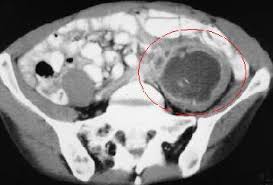

Υπολογιστική Τομογραφία

Η αξονική τομογραφία (CT) έχει ακρίβεια μεγαλύτερη από 95% και είναι η καλύτερη διαγνωστική απεικονιστική μέθοδος για κοιλιακό απόστημα.

Η παρουσία ειλεού, επιδέσμων, παροχετεύσεων ή στομίων δεν επηρεάζει την αξιοπιστία.

Για καλή ανατομική ανάλυση, χρησιμοποιήστε στοματική και ενδοφλέβια (IV) αντίθεση